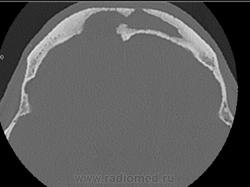

- тотальное снижение пневматизации обоих половин лобных пазух, обоих гайморовых пазух, передней и средней групп ячеек решетчатого лабиринта с двух сторон патологическим содержимым плотностью +17+23HU. Устья гайморовых пазух блокированы патологическим субстратом.

-определяются костные дефекты задней стеки правой половины лобной пазухи, определяется дефект перегородки, разделяющей половины лобной пазухи, дефект передней части костной стенки левой половины лобной пазухи. Дефект верхне-медиального отдела крыши правой орбиты.

-признаки хронического остемиелита в виде неравномерного утолщения костных стенок (гиперостоз) обоих гайморовых пазух, обоих половин лобной пазухи, истончение и изъеденность стенок средней группы ячеек решетчатого лабиринта справа, изъеденность медиальной стенки орбиты (бумажная пластинка решетчатой кости) справа. Патологических изменений со стороны ретробульбарной клетчатки, содержимого орбиты достоверно не выявлено.